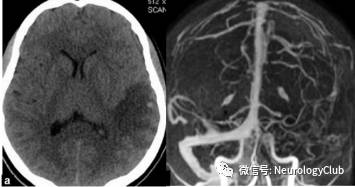

数个研究显示PRES血管造影检查(CTA、MRA、DSA)可见脑血管不规则伴局部血管收缩。研究发现约15-30%患者存在血管收缩。有研究报道17-38%的可逆性脑血管收缩综合征患者伴发PRES。

(图16:可逆性脑血管收缩综合征DSA腊肠样表现)

(图18:静脉窦血栓形成的影像学表现[CT&DSA]